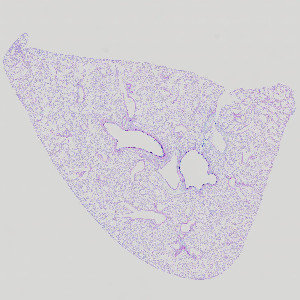

Rodent lung after exposure to house dust mite (HDM), stained with AB/PAS.

Pulmonary mucous cell metaplasia (MCM) is a remodeling process where bronchial epithelial cells undergo metaplasia to mucous cells. This causes an increased production of mucous, which leads to increased airway obstruction. Mucous cell metaplasia is often observed as a feature of allergic airways disease (e.g. asthma) after exposure to an allergen (e.g. house dust mites). The mucosubstances in the epithelium are identified by staining with Alcian Blue (pH 2.5)/Periodic Acid-Schiff (AB/PAS or AB-PAS). Using this APP the degree of mucous cell metaplasia is quantified in pulmonary bronchioles as the volume of mucosubstances per length of basal lamina.